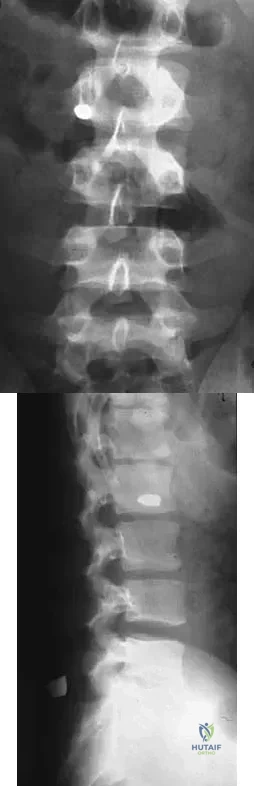

Figure 45 shows the lateral radiograph of a 19-year-old swimmer who has had back pain for the past 2 months. What is the most likely diagnosis?

A 14-year-old competitive gymnast has had activity-related low back pain for the past month. Examination reveals no pain with forward flexion, but she has some discomfort when resuming an upright position. She also has pain with extension and lateral bending of the spine. The neurologic examination is normal. Popliteal angles measure 20 degrees. AP, lateral, and oblique views of the lumbar spine are negative. What is the next most appropriate step in management?